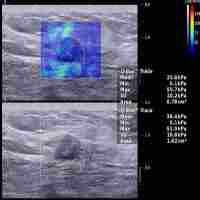

| Abstract | The differential diagnosis of lymphadenopathy is important for predicting prognosis, staging, and monitoring the treatment, especially for cancer patients. Conventional computed tomography and magnetic resonance imaging characterize LN with a disappointing sensitivity and specificity. Conventional ultrasound with the advantage of high resolution has widely used for the Lymph node (LN) evaluation. Ultrasound elastography (UE) using colour map or shear wave velocity can noninvasively demonstrate the stiffness and homogeneity of both cortex and medulla of LNs, and detect the early circumscribed malignant infiltration. There is a need of a review to comprehensively discuss the current knowledge of the applications of various UE techniques in the evaluation of LNs. In this review, we discussed the principles of strain elastography and shear wave-based elastography, and their advantages and limitations in the evaluation of LNs. In addition, we comprehensively introduced the applications of various UE techniques in the differential diagnosis of reactive LNs, lymphoma, metastatic LNs and other lymphadenopathy. Moreover, the applications of endoscopic ultrasound elastography and endobronchial ultrasound elastography are also discussed, including their use for improving the positive rate of diagnosis of fine-needle aspiration biopsy. |